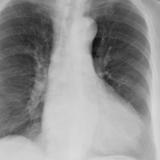

Case 8a Thymoma PA

Date: 03/27/2009

Views: 9451